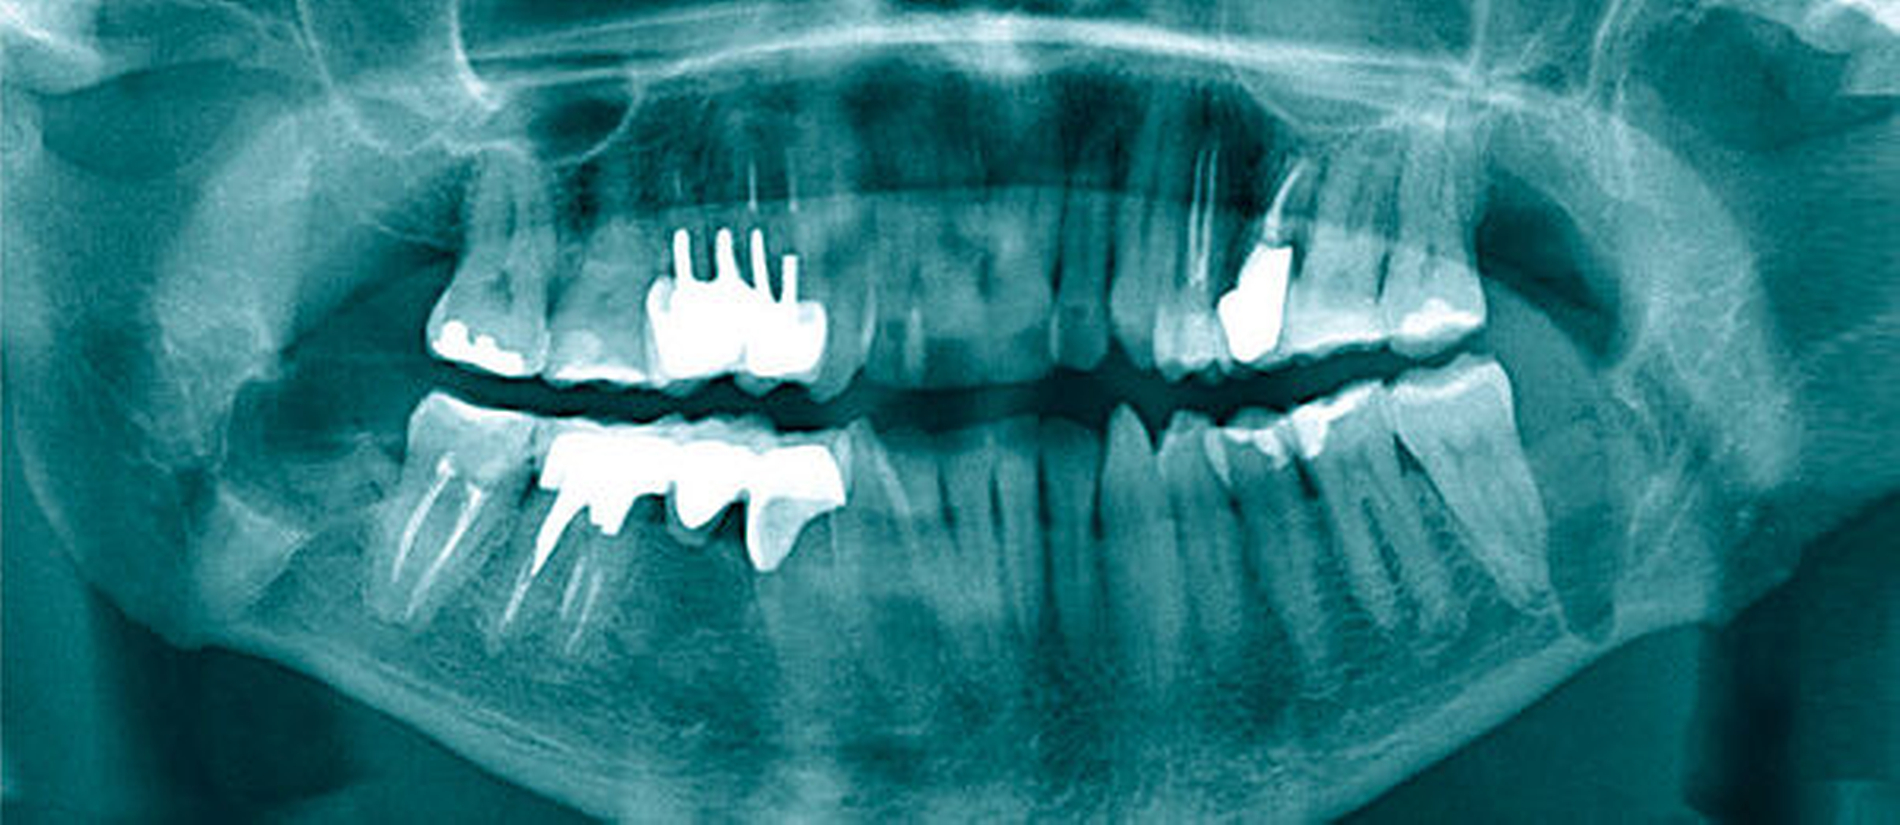

Die vom Kollegen angefertigte Panoramaschichtaufnahme (Abbildung 1) zeigte neben multiplen wurzelgefüllten Zähnen einen in Infraposition befindlichen Zahn 28, einen retinierten Zahn 38 sowie einen retinierten Zahn 48. Da die Zahnwurzeln beider Unterkiefer-Weisheitszähne sehr nah an den Unterkieferrand und in unmittelbarer Nähe zum Mandibularkanal projiziert wurden, entschieden wir uns, eine digitale Volumentomografie (DVT) anzufertigen, um die Lagebeziehung zum Nervus alveolaris inferior weiter abzuklären und die Operation planen zu können.

In der koronaren und der sagittalen Schicht des DVT zeigte sich deutlich die Lage beider Apices in der kaudalen Kompakta des Corpus mandibulae. Zudem wurde ein intraradikulärer Verlauf des Canalis mandibularis rechts durch die Wurzeln des 48 (Abbildung 2) erkannt. Am ebenfalls tief retinierten Zahn 38 konnte relativ zur Wurzel des Zahnes 38 ein lingualer Verlauf des Canalis mandibularis verifiziert werden (Abbildung 3).